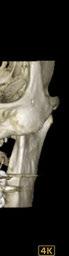

Este caso clínico es un premolar que tiene 3 conductos: sabemos que 2 de ellos son en la raíz vestibular, y

Figura 8. Secuencia operatoria en casos de extrema dificultad instrumental. Figura 9. Recomendación secuencial del tipo de movimiento, dependiendo de la dificultad instrumental del conducto.

39 Gaceta Dental · N o 365 | Abril 2024 Caso clínico. CIENCIA Y CLÍNICA

en el CBCT podemos apreciar a qué longitud del conducto se produce la bifurcación (Figura 10)

Debido a la gran curvatura que se produce en la bifurcación, tenemos que precurvar los instrumentos manuales y rotatorios, para facilitar que los instrumentos alcancen la LT (Figura 11). Terminamos el conducto mesiovestibular y palatino en conicidad .06 y el disto-vestibular en .04 debido al riesgo que pensamos que correríamos si hacemos una secuencia más amplia.